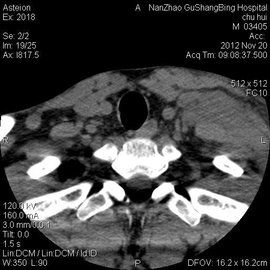

基本診斷

非何杰金氏淋巴瘤對放療及化療敏感,是可治癒性腫瘤,因此早期的診斷非常重要。對於特殊表現的非霍奇金淋巴瘤,臨床表現多種多樣應提高對本病的警覺,特殊表現的非霍奇金淋巴瘤診斷多為晚期,呈侵襲性病程,多有全身症狀發熱、盜汗及衰弱等,療效差。非霍奇金淋巴瘤病理組織學特點:

4.出現較多病理分裂相。活體組織病理學檢查是非霍奇金淋巴瘤鑑別診斷及確診的主要依據,必不可少。與造血系統腫瘤鑑別還需進行骨髓細胞學檢查。

目前本病的病理學診斷已發展為在傳統的形態學基礎上結合免疫學標誌、細胞遺傳學及基因標誌的多指標綜合診斷,從而提高診斷的正確率。